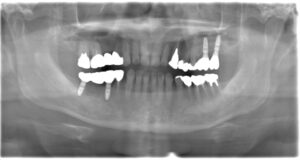

| 備考 | 右上の欠損部へのインプラントを希望で来院されました。 左下のブリッジの下にものが挟まりやすいとのことでブリッジ部分もインプラント埋入を希望されました。口腔内の銀歯も全て綺麗にやりかえたいとのことで、ダイレクトボンディングやセラミックインレーやジルコニアクラウンでやりかえていきました。 右上6番のインプラント埋入時にはソケットリフトで骨造成を行なっています。 見た目だけではなく噛みやすくなりとても満足されています。現在はエアフローのクリーニングやホワイトニングで通院されています。 |